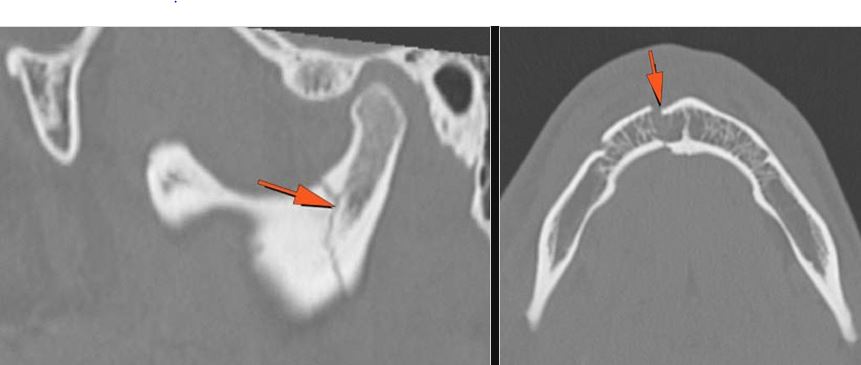

The condylar head and fossa as well as the temporomandibular joint space are abnormal. [Yes/No]

There is condylar fracture either within or outside of the joint capsule, or with or without involvement of the articular surface of the condylar head. [Yes/No]

There is evidence of radiodense intra-articular osteochondral fragments. [Yes/No]

There are dental fractures and/or missing or displaced teeth. [Yes/No]